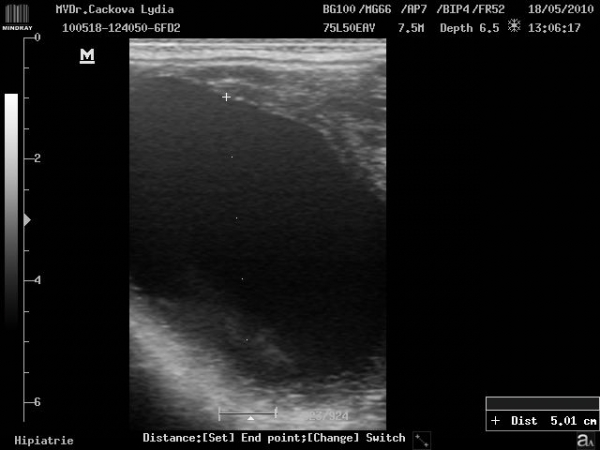

Preovulační folikul